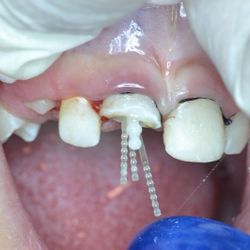

Η νεαρή αυτή ασθενής μας είχε ολοκληρώσει παλαιότερη ορθοδοντική θεραπεία, η οποία είχε οδηγήσει σε νέκρωση τον άνω δεξιό κεντρικό και πλάγιο τομέα.

Τα δόντια αυτά είχαν απονευρωθεί στο παρελθόν και είχαν μαυρίσει.

Τοποθετήθηκαν άξονες υαλονημάτων (ParaPost FiberWhite/Coltene) για ενίσχυση των ριζών και στη συνέχεια χτίστηκαν όψεις ρητίνης (Herculite XVR Ultra/Kerr) για να διορθωθεί η δυσχρωμία τους.